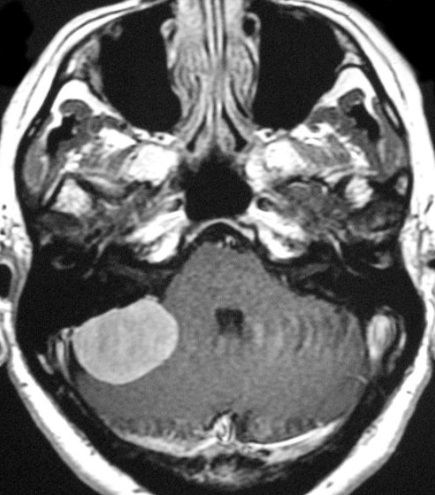

6. Rare Causes

Tumours, vascular problems, or neurological conditions (usually one-sided tinnitus).

- Imaging (CT/MRI) when indicated